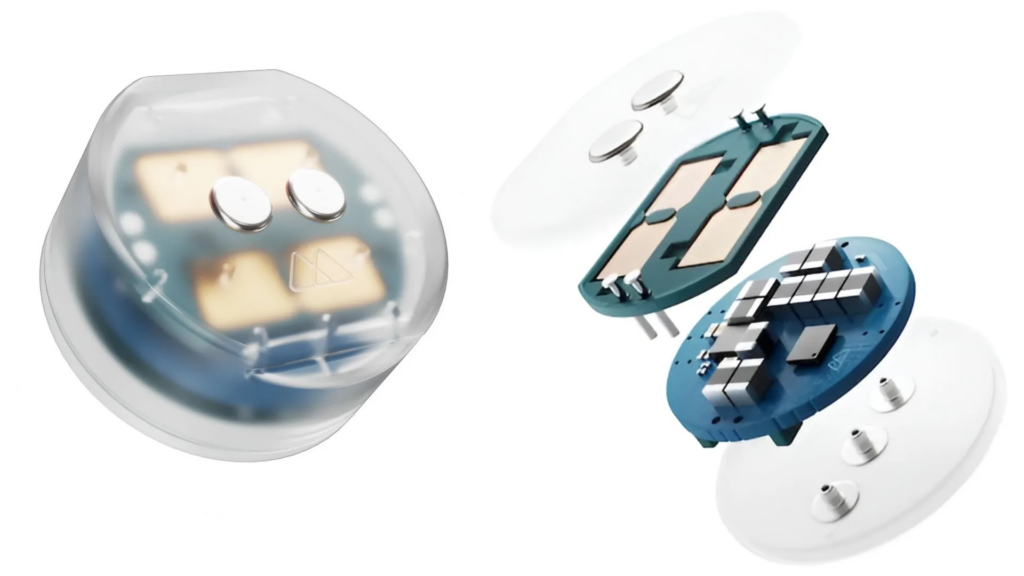

Geliştirilen cihaz, yaklaşık bir yaban mersini büyüklüğünde küçük bir implant olarak tasarlanıyor. Kafatasına, beynin koruyucu zarı olan dura materin üst kısmına yerleştiriliyor. Bu sayede daha derin beyin bölgelerine girilmeden, daha az invaziv bir çözüm ortaya çıkıyor.

Bu teknolojinin dikkat çeken yönlerinden biri kablosuz çalışması oluyor. İmplant, enerjisini dışarıdan manyetoelektrik bir sistem aracılığıyla alıyor. Bu enerji, hastanın başına taktığı özel bir aparat üzerinden iletiliyor.

Tedavi sürecinde kullanıcıların günde birkaç kez, yaklaşık 10 ila 20 dakika süren seanslarla bu sistemi kullanması planlanıyor. Bu yaklaşım, hastane ortamına bağlı kalmadan evde uygulama imkanı sunuyor. Özellikle uzun süreli tedavi ihtiyacı olan kişiler için daha pratik bir süreç anlamına geliyor.